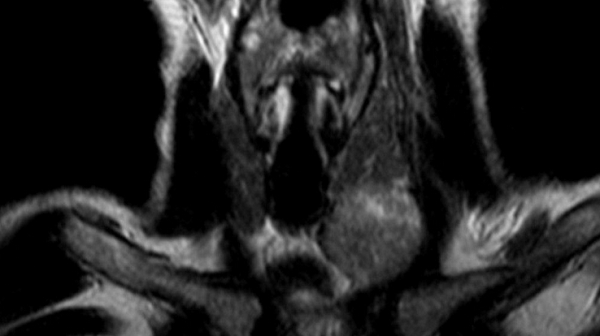

Снимки МРТ мягких тканей шеи

Проведение магнитнорезонансной томографии с использованием различных режимов повышает информативность исследования рыхлых элементов. Изучение особенностей кровоснабжения зоны интереса и диагностика новообразований требуют применения контрастного раствора. В качестве «окрашивающего» препарата используют хелаты гадолиния.

Мягкие ткани шеи на МРТ

Магнитно-резонансное сканирование может применяться в качестве основного или дополнительного метода исследования в диагностике эндокринных заболеваний.